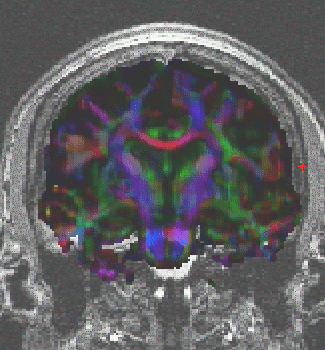

Diffusion tensor imaging

YC_DTI1